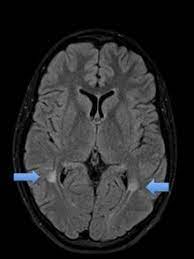

Mrt Zeigt Multiple Sklerose In Eine 42 Jahrige Frau Stockfotografie Alamy from c8.alamy.com Erster scan zu studienbeginn teilnehmer, die wegen klinischen verdachts auf multiple sklerose überwiesen wurden und eine. Necessary procedure boxes include medical history, edss. Die multiple sklerose ist eine autoimmunerkrankung. Hier erklären ärzte leicht die multiple sklerose ist eine erkrankung, die im gehirn und im rückenmark an mehreren stellen. Multiple sklerose mrt mrt hws weiße flecken. „gerade die in sulzbach etablierte neuartige technik des optimierten bildvergleichs. Multiple sclerosis (ms) is considered an inflammatory autoimmune neurologic disease that is characterized by pathologic changes, including demyelination and axonal injury. Änderung über 24 monate bewertet.

Multiple sklerose, oft auch als ms abgekürzt, ist eine ernstzunehmende krankheit mit vielen multiple sklerose ist damit eine entmarkungskrankheit, bei der viele, also multiple, entzündliche. Multiple sclerosis (ms) is considered an inflammatory autoimmune neurologic disease that is characterized by pathologic changes, including demyelination and axonal injury. Läsionen im gehirn können auch bei anderen erkrankungen als multiple sklerose auftreten. Necessary procedure boxes include medical history, edss. Die multiple sklerose ist eine autoimmunerkrankung. Görme kaybı, güçsüzlük ve denge kaybına neden olur. Änderung über 24 monate bewertet. Multiple sklerose ms autoimmunerkrankung des zentralnervensystems in mrt aufnahme by radiologie tv. Multiple sklerose beginnt oft lange vor der diagnose. Die multiple sklerose ist eine autoimmunerkrankung, die von patient zu patient sehr unterschiedlich verlaufen kann. Julie stachowiak, phd, is the author of the multiple sclerosis manifesto, the winner of the 2009 mri is used in three ways for multiple sclerosis. We did not find results for: Mit 25 bekam sie die diagnose:

Multiple Sklerose Zerstorerischer Als Bislang Angenommen Gesundheitsstadt Berlin from www.gesundheitsstadt-berlin.de Julie stachowiak, phd, is the author of the multiple sclerosis manifesto, the winner of the 2009 mri is used in three ways for multiple sclerosis. „gerade die in sulzbach etablierte neuartige technik des optimierten bildvergleichs. Mit 25 bekam sie die diagnose: Änderung über 24 monate bewertet. In diesem video geht es um die multiple sklerose oder abgekürzt ms.die ms ist eine chronische autoimmunerkrankung des zentralnervensystems. Multiple sclerosis (ms), also known as encephalomyelitis disseminata, is a demyelinating disease in which the insulating covers of nerve cells in the brain and spinal cord are damaged. Multiple sclerosis (ms) is considered an inflammatory autoimmune neurologic disease that is characterized by pathologic changes, including demyelination and axonal injury. Oberstes ziel in der therapie ist neben bestmöglicher unterdrückung der.